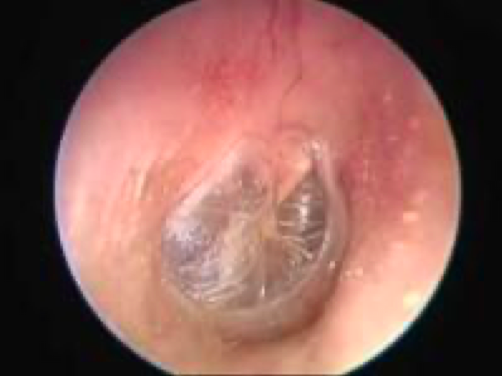

Patulous ET

Patulous tube

Causes of patulous ET and sx

extensive weight loss

pregnancy

sx: autophony